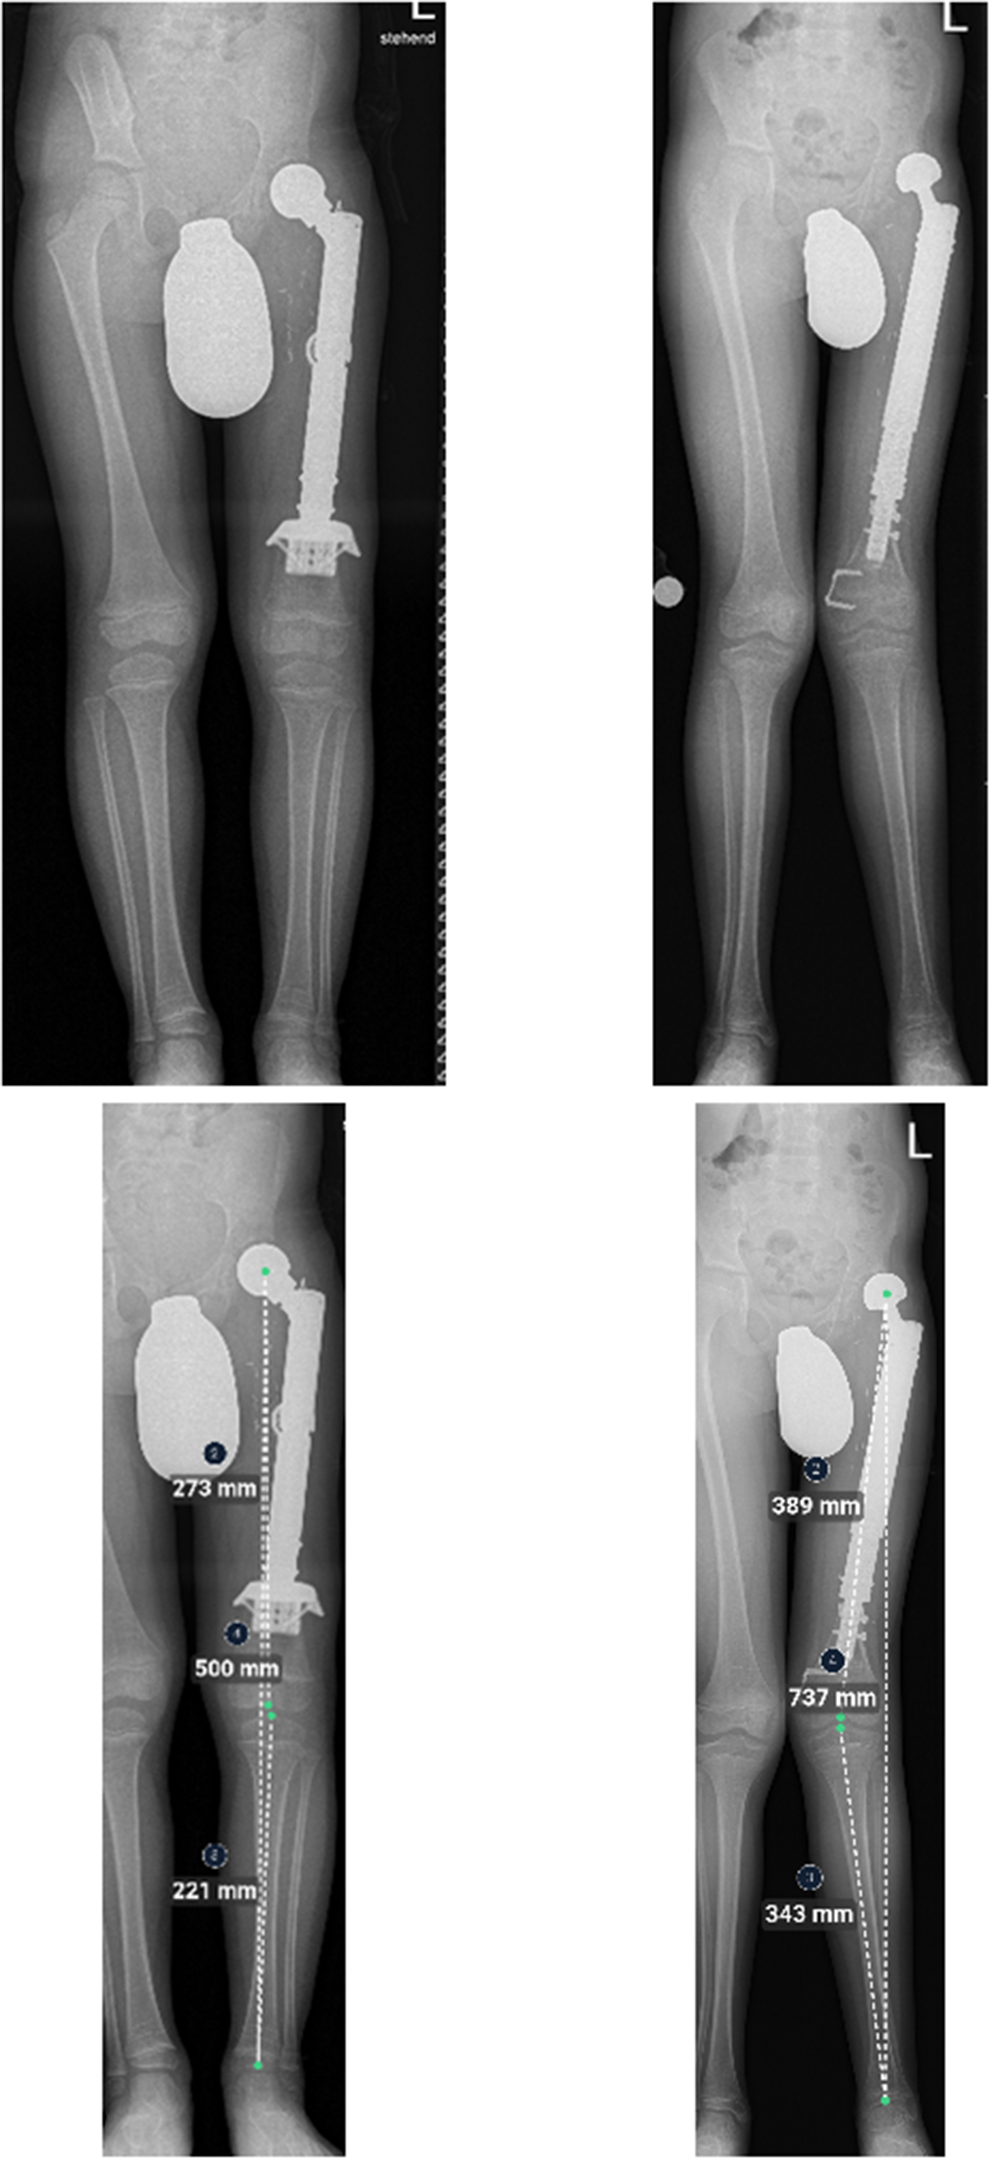

Five patients (n = 5/12; 41.6%) aged 4–11 years at the time of primary reconstruction developed varying clinical degrees of genu valgum (Table 3). In four patients, a distal femoral cause (pathological mechanical lateral distal femur angle (mLDFA)) was identified. In patient #10 the deformity was bilateral and complex; caused by both pathological mechanical femur and tibia angles. In patient #7 a temporary hemiepiphyseodesis of the distal medial femur epiphysis was performed (Fig. 4), whereas patient #10 underwent bilateral temporary hemiepiphyseodesis of the proximal medial tibia epiphyses despite his young age.

Fig. 4

7-year-old patient (#7) with a Ewing’s sarcoma of the left femur. Top and bottom left: A.p. x-rays immediately and 16 months after the operation. A custom-made non-plated hollow stem was used to preserve the distal femoral growth plate. The patient presents with a lateralization of the bipolar head (bottom). Continuous growth of the distal femoral growth plates is apparent (visible temporary growth arrest lines and lengthening of the remaining distal femur). Center: Full-length standing a.p. x-ray 28 months after primary proximal femur replacement and 6 months after temporary hemiepiphyseodesis of the medial distal femoral growth plate for femoral genu valgum. Progressive lateralization of the bipolar head. Right: Full-length standing a.p. x-ray 43 months after primary and 21 months after temporary hemiepiphyseodesis surgery with a visible correction of the genu valgum deformity

While pathological mechanical lateral distal femur angles coincided with hip dysplasia in three patients (n = 3/7; 42.9%) (Fig. 5), two patients without signs of hip dysplasia were affected by genu valgum as well.

Full-length standing a.p. x-rays of patient #9 (left) and #7 (right). Left: Normal alignment in the frontal plane after proximal femur replacement. The mechanical axis passes through the center of the knee joint. Right: Genu valgum in the frontal plane. The mechanical axis is deviated and passes lateral to the center of the knee joint without making contact with the lateral femur condyle